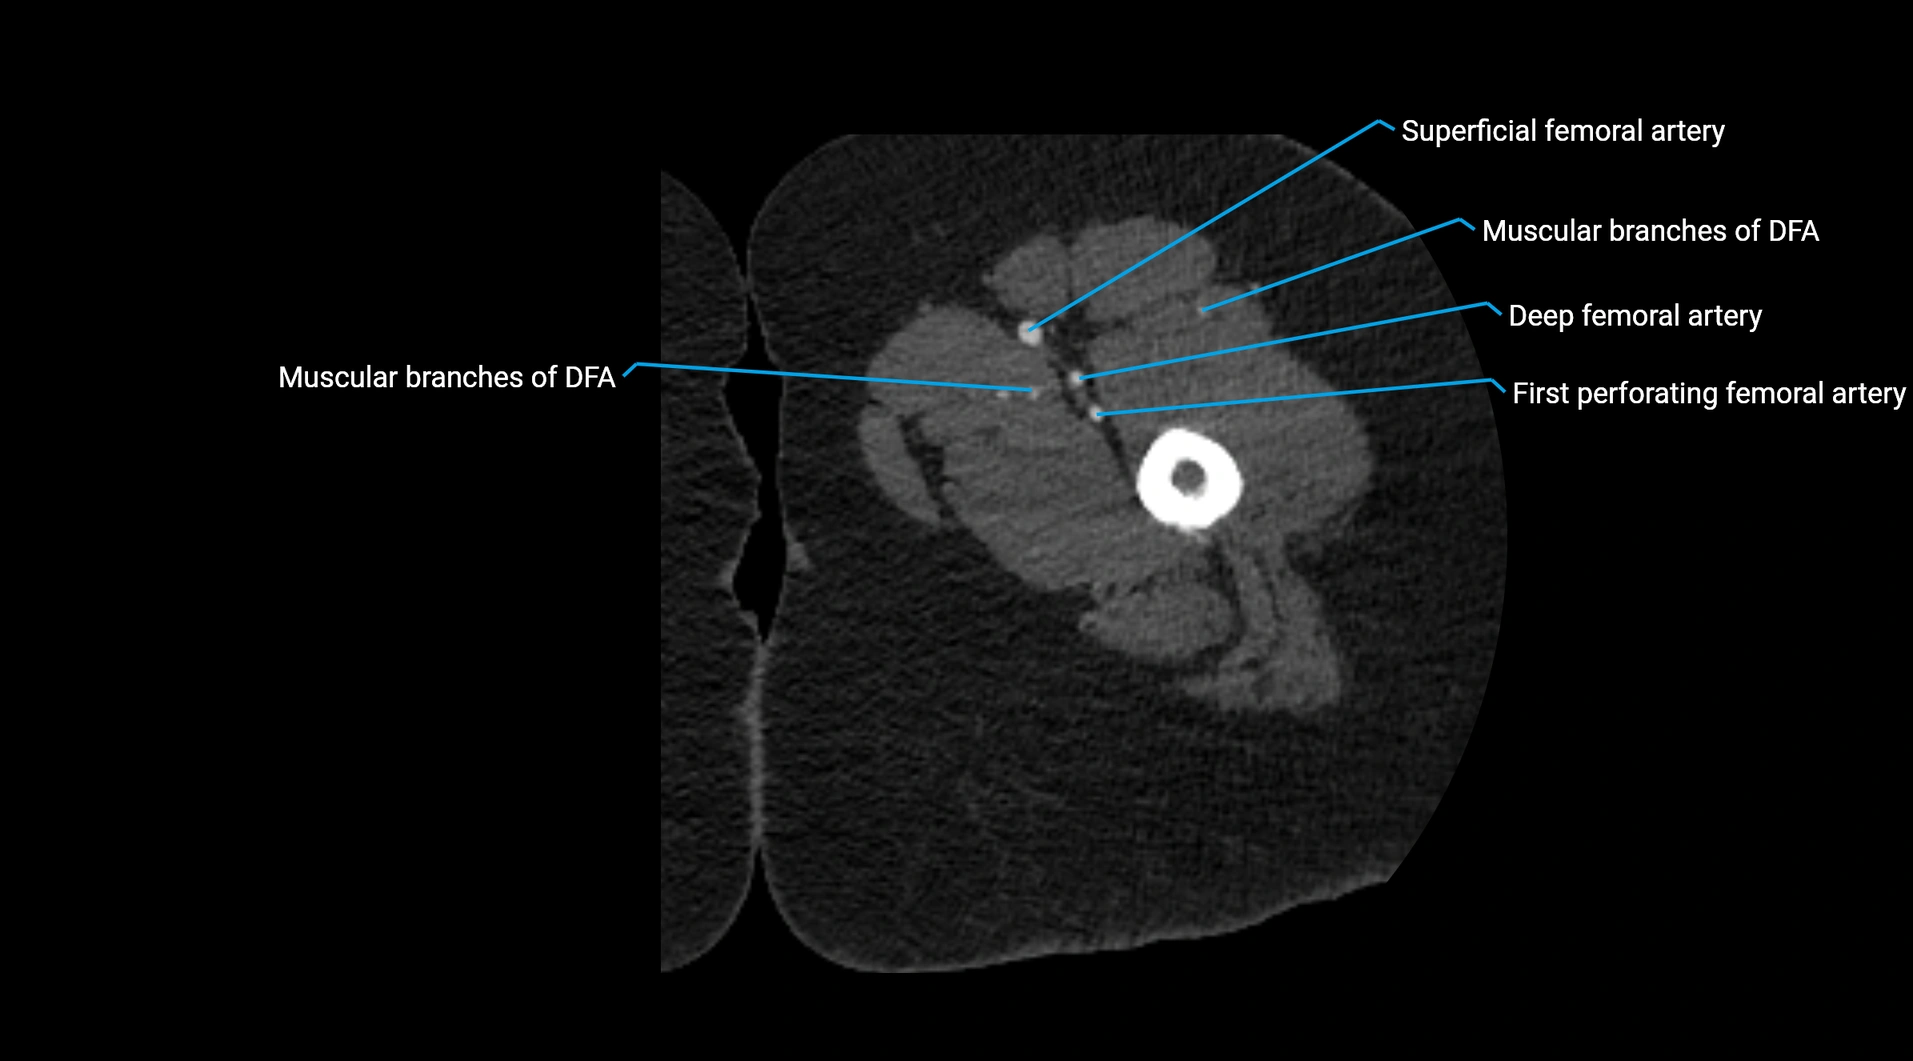

CT images

image

Contrast-enhanced CT (CTA):

• Gold standard for abdominal aortic imaging

• Provides excellent detail of lumen, wall, aneurysm, thrombus, and branch vessels

• Multiplanar and 3D reconstructions help in aneurysm measurement, stent graft planning, and dissection evaluation

• Detects acute rupture, traumatic injury, or occlusion with high sensitivity